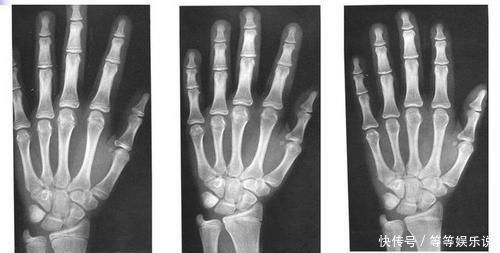

2、测骨龄

这种方式较为准确科学,可到正规的医院给孩子拍个骨龄片子,医生会告诉你是否发育存在滞后的问题。

毕竟现在的孩子生活水平高,普遍存在早熟问题,若骨龄超前,也会导致身高发育受限。